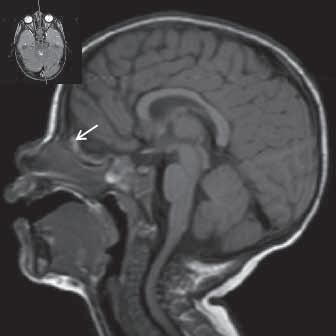

Obr. I.1.1c Fyziologické změny v závislosti na věku baze lební a corpus callosum, hypersignál v přední části kosti klínové (žlutá kostní dřeň) ve 2 roce života (šipka)

Obr. I.1.1d Fyziologické změny v závislosti na věku baze lební a corpus callosum, zvýšený signál v oblasti celé kosti klínové a klivu (žlutá kostní dřeň) (šipka), dochází k pneumatizaci a vývoji sinus sfenoidalis (přerušovaná šipka) ve 4 roce života